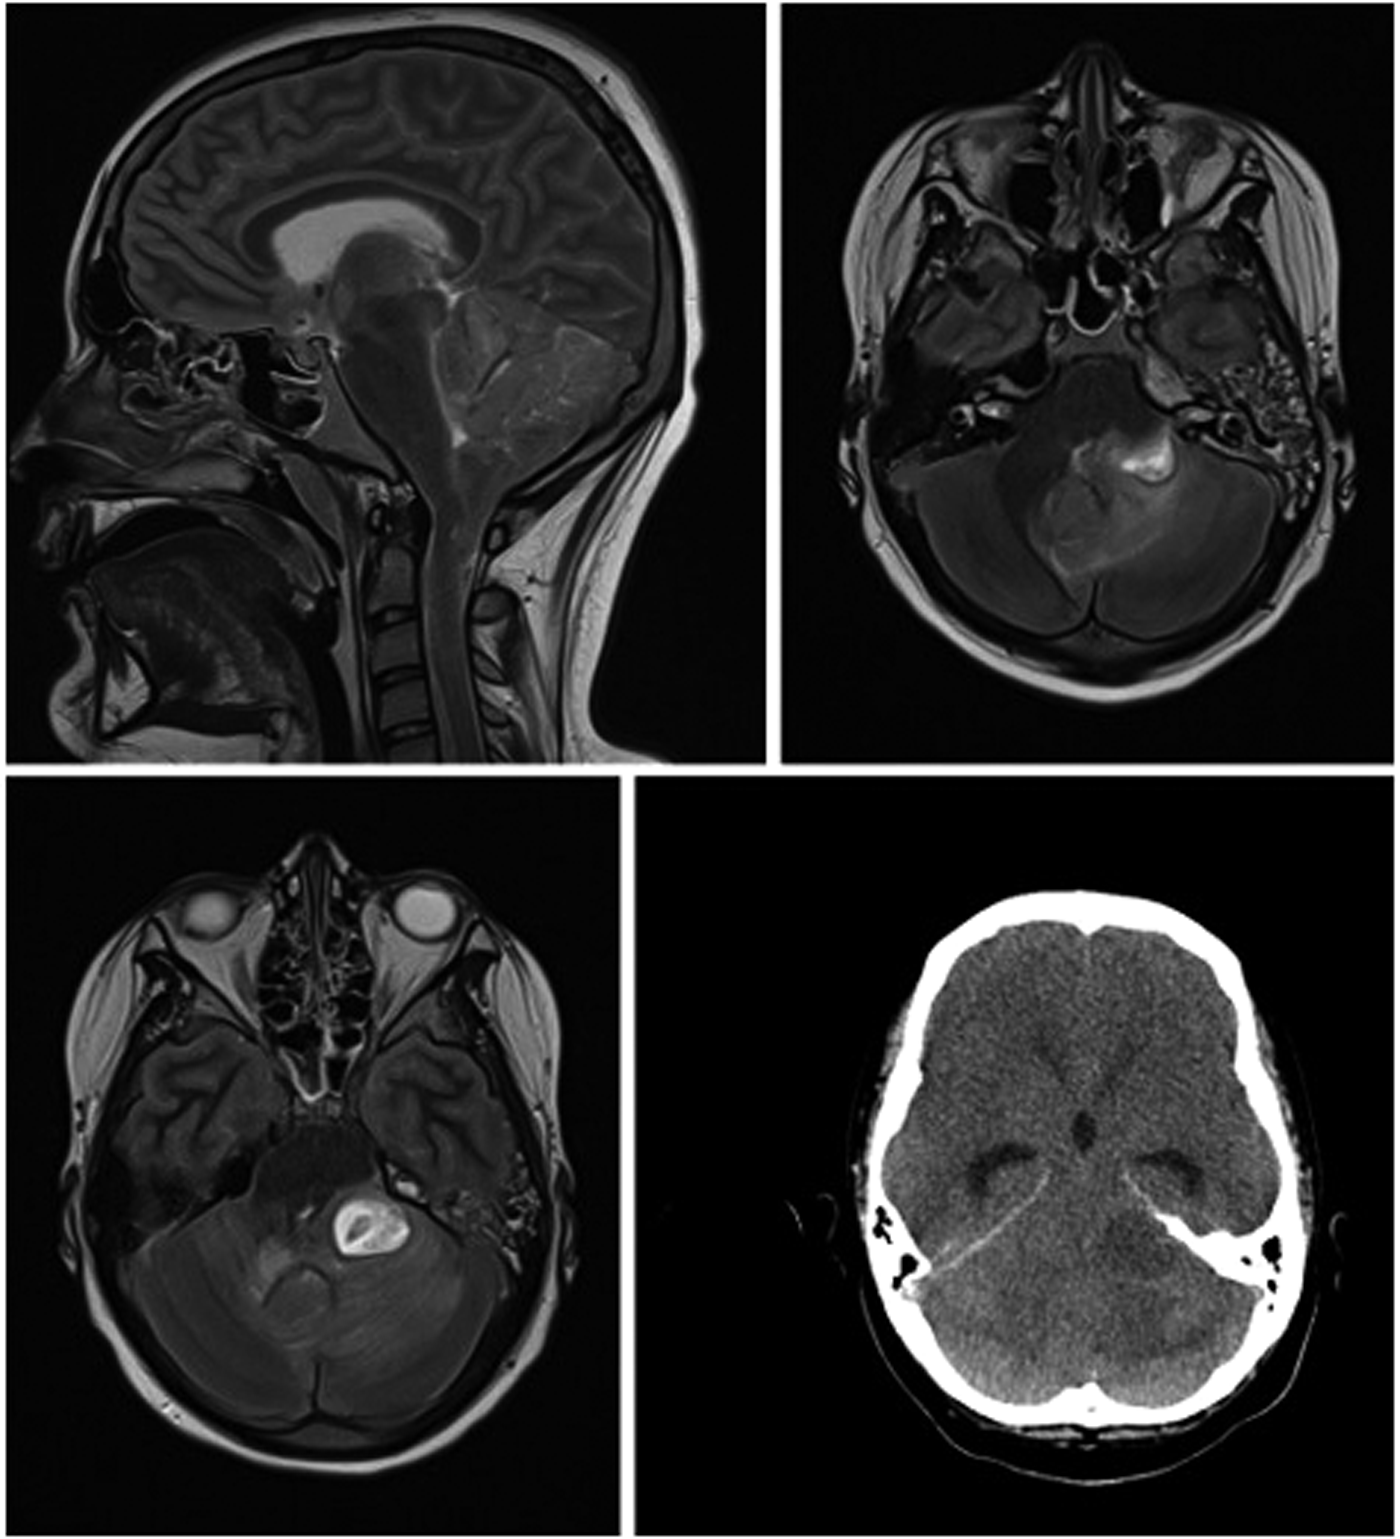

We present the case of a 13-year-old boy with obesity and hypertension who unexpectedly needed to be resuscitated at home by his mother (for the timeline see Figure 1). When the emergency physician arrived half an hour later, pupils were already dilated. After more than 30 minutes of professional resuscitation with intubation, administration of adrenaline and multiple defibrillations, spontaneous circulation was achieved. Intubated and ventilated, the patient was then admitted to our pediatric intensive care unit (PICU), where we performed a cranial computed tomography (CT) and, in the course, a cranial magnetic resonance imaging (MRI), in which the clinical suspicion of a lower entrapment was confirmed. The most likely cause appeared to be the caudal ectopia of the cerebellar tonsils and a cystoid mass in the left cerebellopontine angle compressing the brainstem, with prominent surrounding cerebellar edema and inflammatory changes in the area of the petrous bone and the left mastoid (see Figure 2). Laboratory results on admission are shown in Table 1.

Figure 2

cMRI and cCT show lower entrapment most likely caused by caudal ectopia of the cerebellar tonsils and a cystoid mass in the left cerebellopontine angle compressing the brainstem, with prominent surrounding cerebellar edema and inflammatory changes in the area of the petrous bone and the left mastoid.